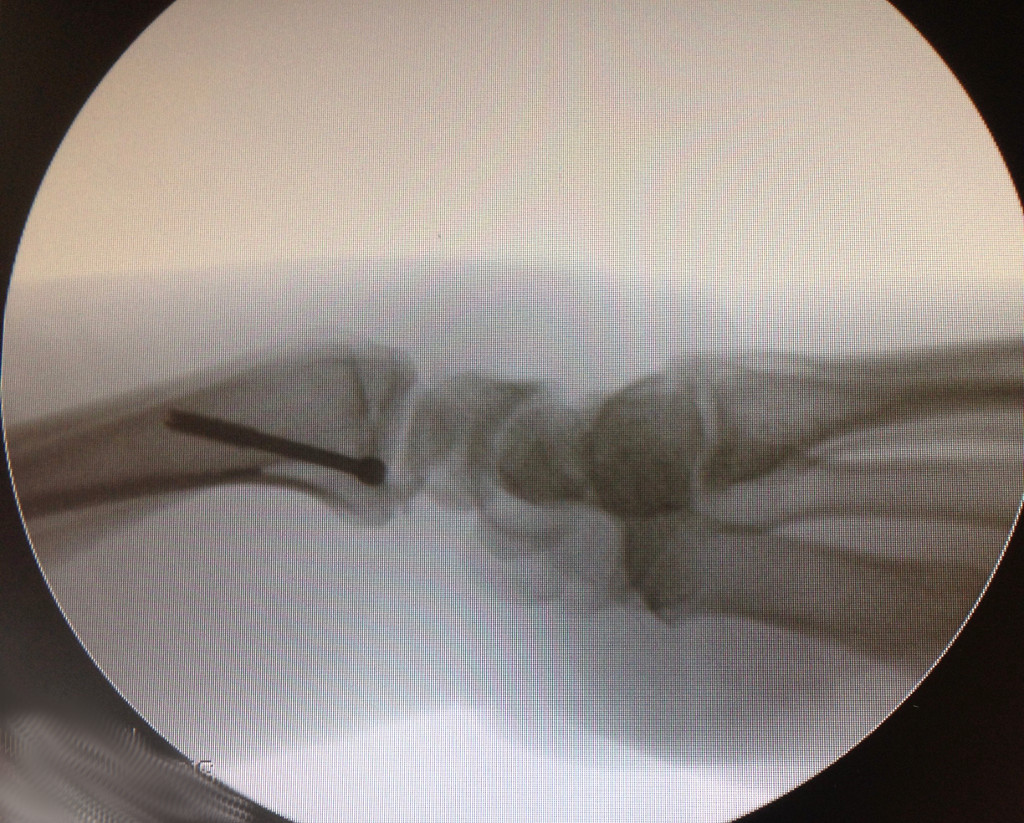

Il s'agit d'une technique relativement récente apparue au début des années 1990, utilisant une caméra et des instruments miniaturisés, pouvant être introduit par des orifices de quelques millimètres dans le poignet. Le chirurgien peut donc explorer l'ensemble des éléments anatomiques situés dans l'articulation via la caméra et un écran vidéo. Cette technique permet un diagnostic précis des différentes lésions articulaires et permet également de traiter un certain nombre de ces lésions.

INDICATIONS

Outre une exploration précise du cartilage, des ligaments, de la mobilité des différents os entre eux, cette technique va permettre de traiter un certain nombre de lésions.

- Une rupture ligamentaire.

- En cas de fracture ou de séquelles de fracture, Des fragments osseux ou cartilagineux fracturés pourront être remis en place et fixés.

- En cas de désinsertion du ligament triangulaire, celui-ci pourra être suturé sous contrôle arthroscopique.

- En cas de fracture du scaphoïde, un éventuel brochage ou vissage de la fracture pourra être contrôlé parfaitement par cette technique.

- Un kyste synovial pourra être complètement enlevé par l'intérieur de l'articulation.

INTERVENTION

Sous anesthésie régionale, le bras du patient est placé dans un système de traction. Un arthroscope de 2,5mm est alors introduit dans l'articulation, de même que de petits instruments pour explorer le poignet et débrider les ligaments déchirés ou ronger le cartilage usé.